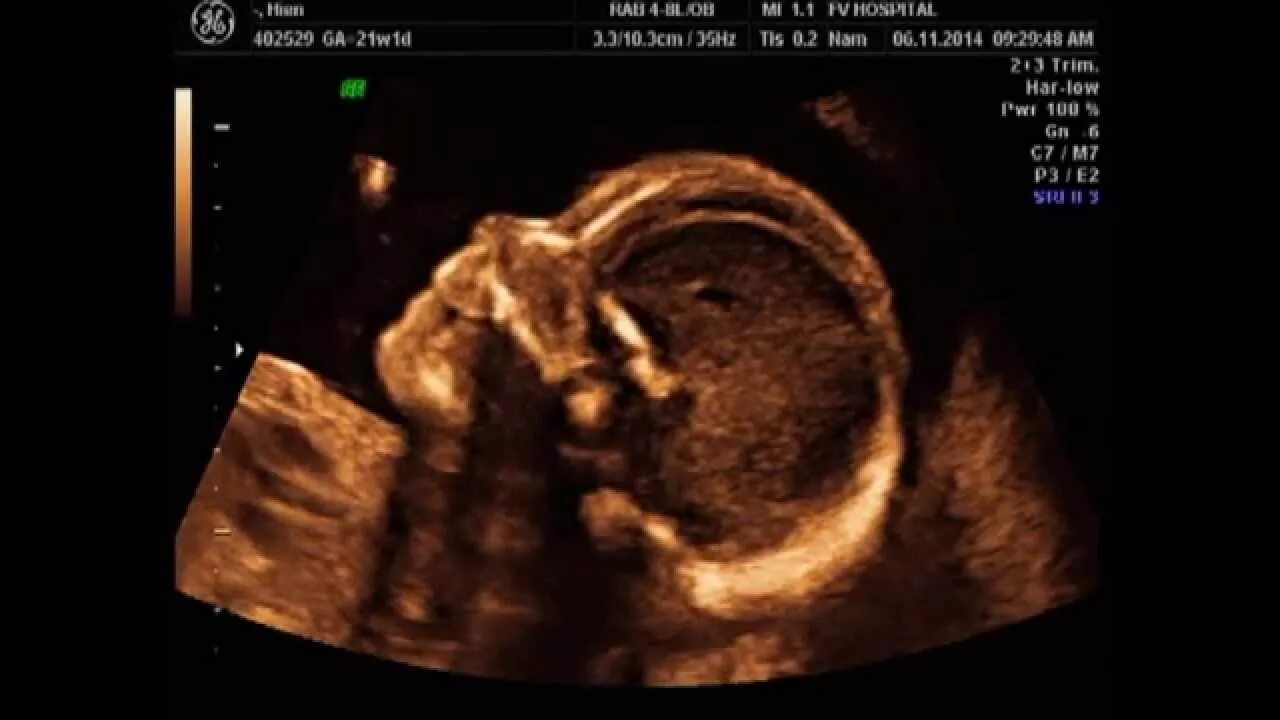

21 неделя и 4 дня